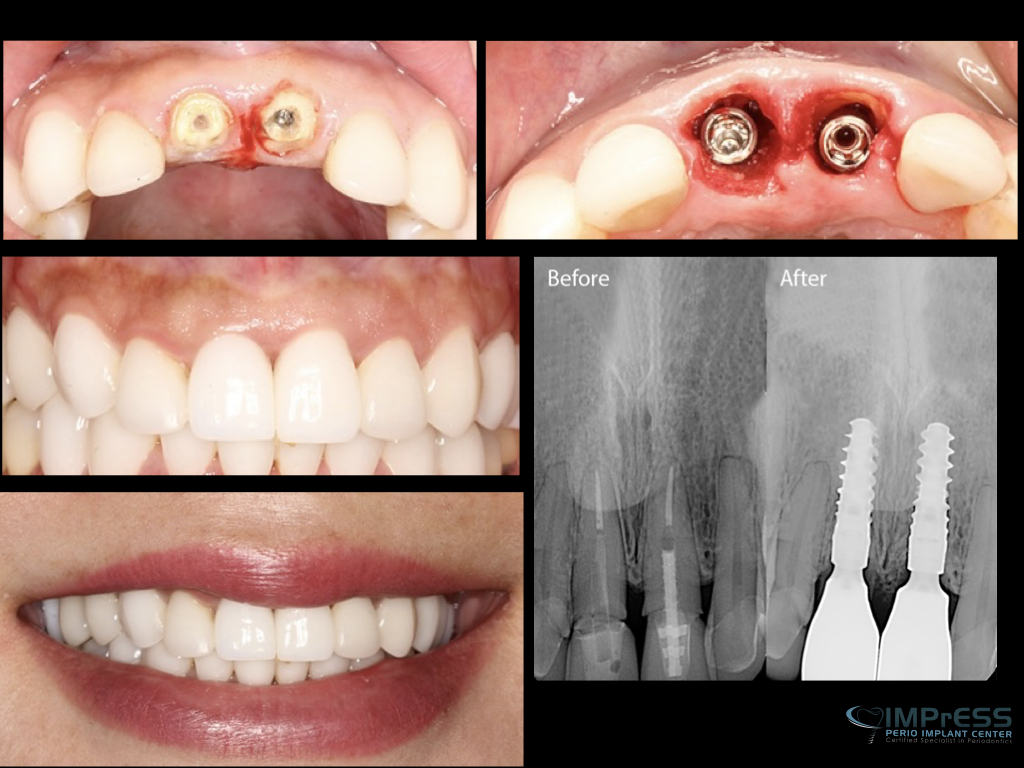

Before & Afters of Dental Implant Patients

Complete Dental Implant Cases Gallery

• During the second stage of surgery and once the tissue is healed, your dentist or specialist will attach an abutment to the implant. An abutment is a post that connects the replacement tooth to the implant. In some cases, the first and second stage of implant surgery may be done in one single stage.

• An artificial replacement tooth is made and your dentist or specialist attaches it to the abutment. It may take several appointments to properly fit the replacement tooth to the abutment.

General Disclaimer: The results in the photographs are examples only and do not imply any certainty of the result of a procedure, and all outcomes are subject to the circumstances of the individual patient.